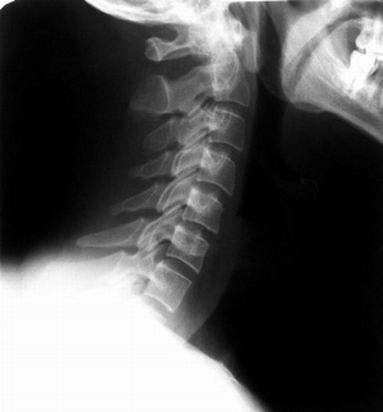

从侧面看,颈椎的部分向前弯曲,呈反括号状,如果颈椎的弧度消失或呈正括号状,就是颈椎反弓。人的脊柱由30多节椎骨组成,从正面看,脊柱是一条笔直的粗线,如果脊柱向左向右弯曲,不是一条直线,就是脊柱侧弯。(王真)